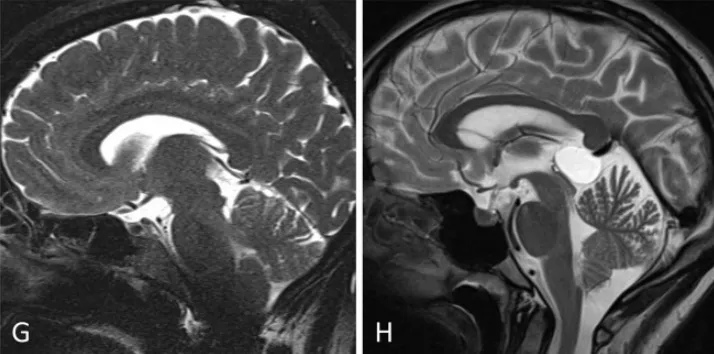

小腦幕傾斜度變異分析:旁正中入路(G)至松果體區(qū)的視角軌跡較中線入路(H)更為平緩。

小腦幕傾斜度變異分析